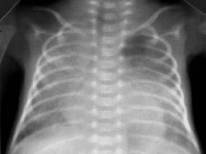

Резкое снижение пневматизации легких, воздушные бронхограммы, границы сердца не различимы, "белые лёгкие" (Рис.7).

Рисунок 7 . РДС. Рентгенограмма грудной клетки в прямой проекции, в горизонтальном положении. Интенсивное мелкоточечное затемнение легочных полей - симптом "матового стекла", на фоне которого не дифференцируется тень средостения. Визуализируются линейные просветления, обусловленные заполненными воздухом бронхами - "воздушная бронхограмма". ( Диагностика и лечение РДС недоношенных // метод. рекомендация, 2007)